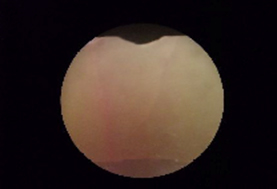

治療前:赤い部分は歯が溶けている部分

治療後:赤い部分が消えて歯が強化された